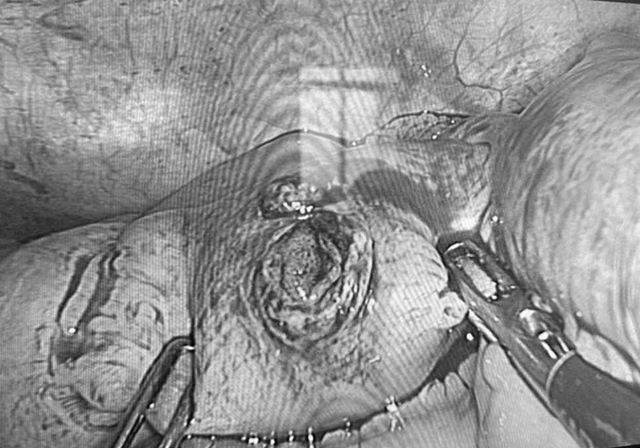

Vết thủng ở ruột non người bệnh.

Vết thủng ở ruột non qua màn hình và chiếc đinh được các bác sĩ phẫu thuật nội soi lấy ra.